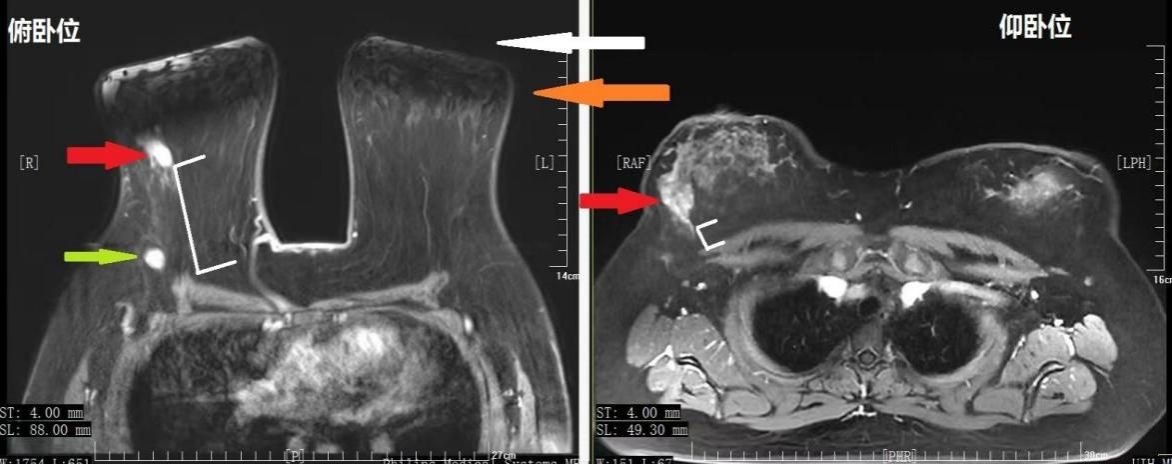

图1 俯卧位与仰卧位对比 患者舒适度增加

图3 超大乳房俯卧位MRI图像常规俯卧位乳腺前部接触底板,形态异常,无法评估局部情况